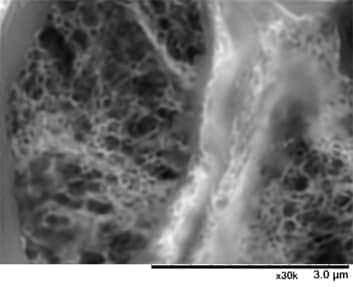

稻贺教授指出“低真空SEM和传统TEM、光学显微镜主要的区别是:它可以实现立体观察和三维成像。”“Alport综合症是在基底膜形成网状结构,之前我们一直采用TEM观察切片的二维图像来判断是否发生病变,如篮状细胞的观察,现在我们可以使用低真空SEM观察它真实的三维结构。”

Alport综合症为遗传性疾病,其主要特征是肾小球基底膜发生病变。薄基底膜肾病也是由于肾小球基底膜发生病变引起的,Alport综合症患者往往在青壮年时期发展至终末期肾脏病,必须通过透析进行治疗。这两种肾病的鉴定对于患者的治疗和预后等具有十分重要的意义。冈田教授提到,“过去我们利用免疫染色或透射电子显微镜进行肾病鉴定,现如今诊断技术已实现遗传基因检测,尽管如此,还是不能诊断出肾病类型,而低真空SEM可全面获取标本数据,快速且准确诊断肾病”。

图示为Alport综合症患者的肾小球在低真空SEM下的图像(PAM染色)。

低真空SEM下清晰呈现基底膜的网状结构。